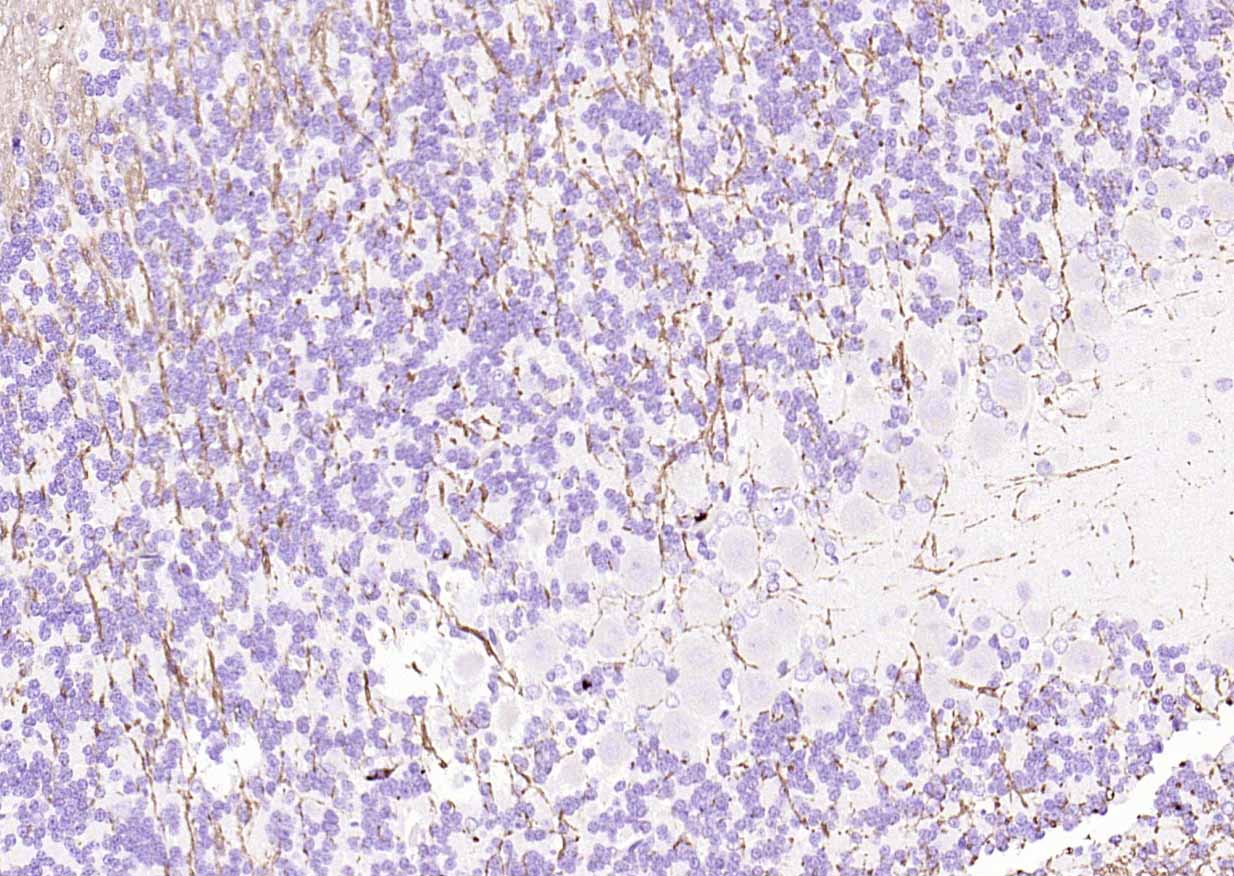

The protein encoded by the classic MBP gene is a major constituent of the myelin sheath of oligodendrocytes and Schwann cells in the nervous system. However, MBP-related transcripts are also present in the bone marrow and the immune system. These mRNAs arise from the long MBP gene (otherwise called "Golli-MBP") that contains 3 additional exons located upstream of the classic MBP exons. Alternative splicing from the Golli and the MBP transcription start sites gives rise to 2 sets of MBP-related transcripts and gene products. The Golli mRNAs contain 3 exons unique to Golli-MBP, spliced in-frame to 1 or more MBP exons. They encode hybrid proteins that have N-terminal Golli aa sequence linked to MBP aa sequence. The second family of transcripts contain only MBP exons and produce the well characterized myelin basic proteins. This complex gene structure is conserved among species suggesting that the MBP transcription unit is an integral part of the Golli transcription unit and that this arrangement is important for the function and/or regulation of these genes.

| 应用 | 已检合格种属 | 预测种属 | 推荐稀释比例 |

|---|---|---|---|

| WB | Mouse, Rat | Human, Rabbit, Pig, Sheep, Cow, Dog, Horse | 1:1000-5000 |

| IHC-P | Human, Mouse, Rat | Rabbit, Pig, Sheep, Cow, Dog, Horse | 1:500-2000 |

| IHC-F | Human, Mouse, Rat | Rabbit, Pig, Sheep, Cow, Dog, Horse | 1:500-2000 |

| IF | Human, Mouse, Rat | Rabbit, Pig, Sheep, Cow, Dog, Horse | 1:500-2000 |

| Flow-Cyt | Rat | Human, Mouse, Rabbit, Pig, Sheep, Cow, Dog, Horse | 1:100-200 |

交叉反应: Human, Mouse, Rat (predicted: Rabbit, Pig, Sheep, Cow, Dog, Horse)